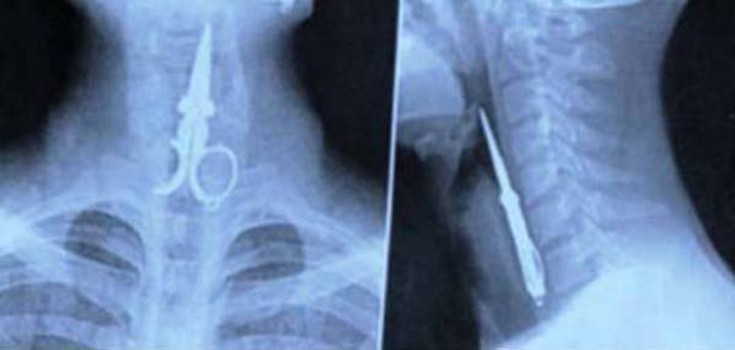

Ο,ΤΙ ΝΑ 'ΝΑΙ #ακτινογραφίες Παράξενα πράγματα που έχουν δείξει οι ακτινογραφίες Από δαχτυλίδια μέχρι πιρούνια και καρφιά - Δείτε τις φωτογραφίες 15·04·2016 11:08 1 σχόλια